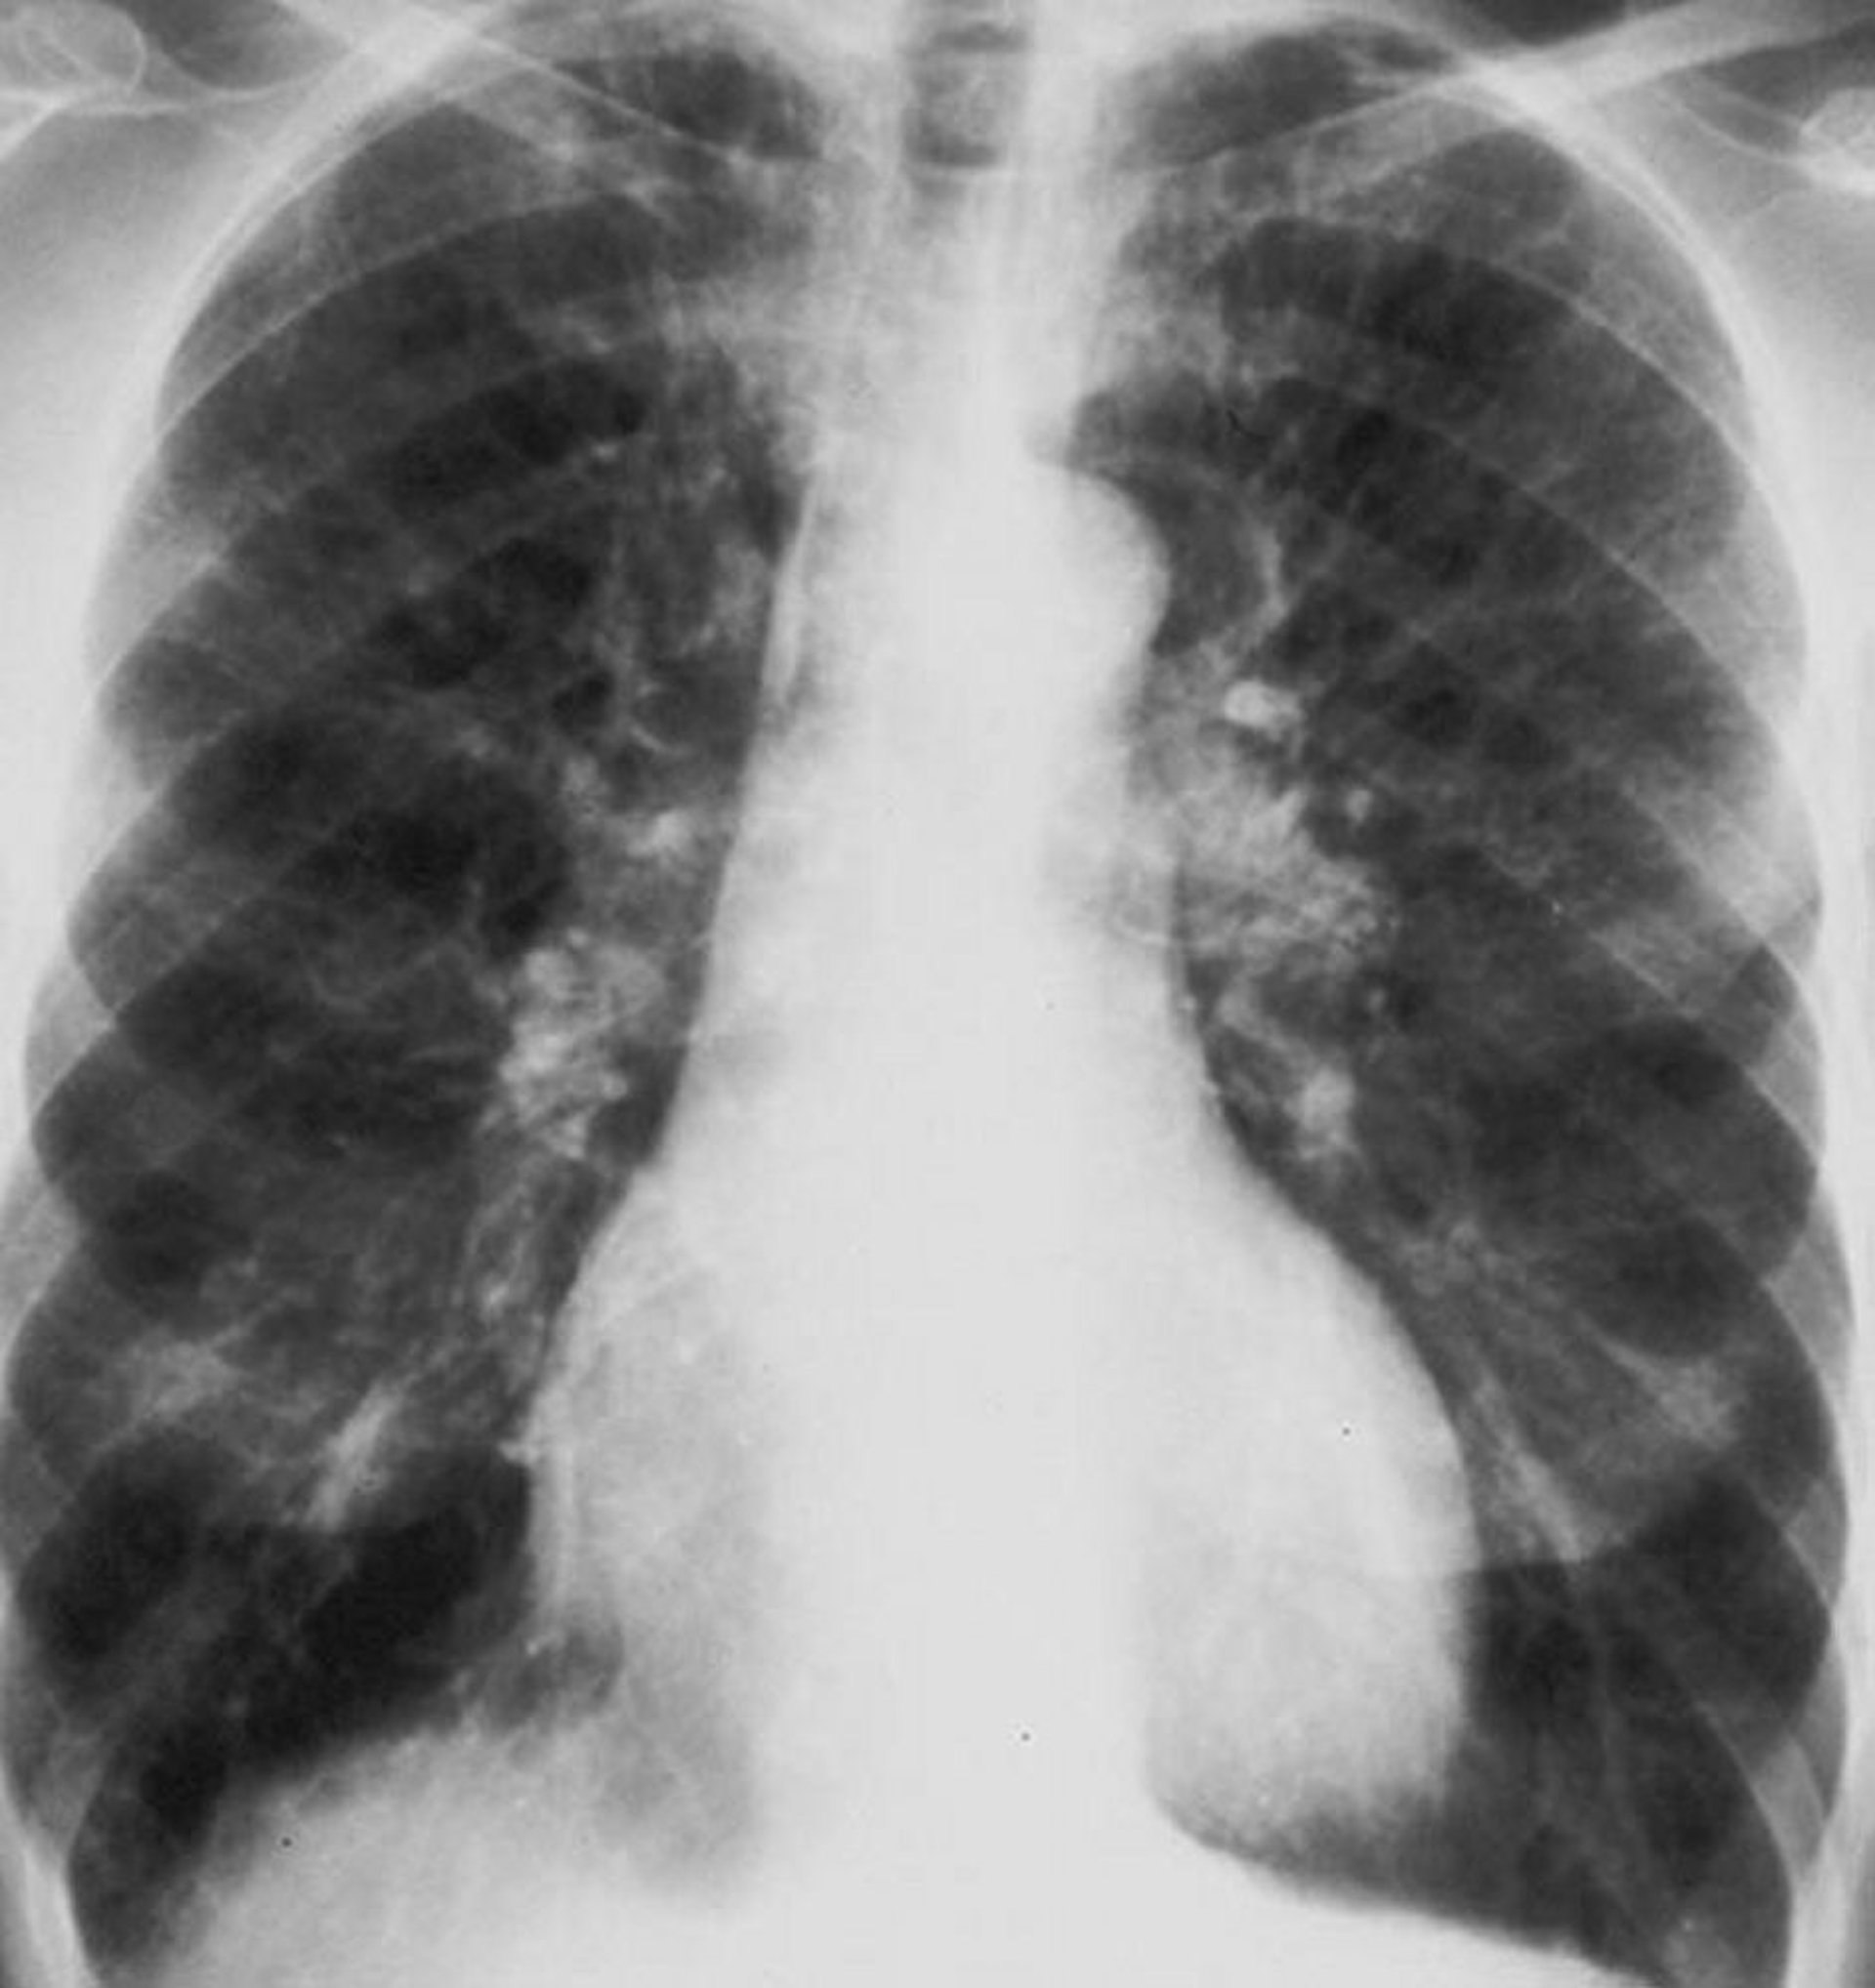

Doença pulmonar obstrutiva crônica (radiografia de tórax)

Radiografia de tórax de um paciente com doença pulmonar obstrutiva crônica (DPOC). Os pulmões estão hiperinsuflados, o diafragma retificado, a trama vascular aumentada e o tamanho do coração discretamente aumentado.

By permission of the publisher. From Barnes P. In Bone's Atlas of Pulmonary and Critical Care Medicine. Edited by J Crapo. Philadelphia, Current Medicine, 2005.